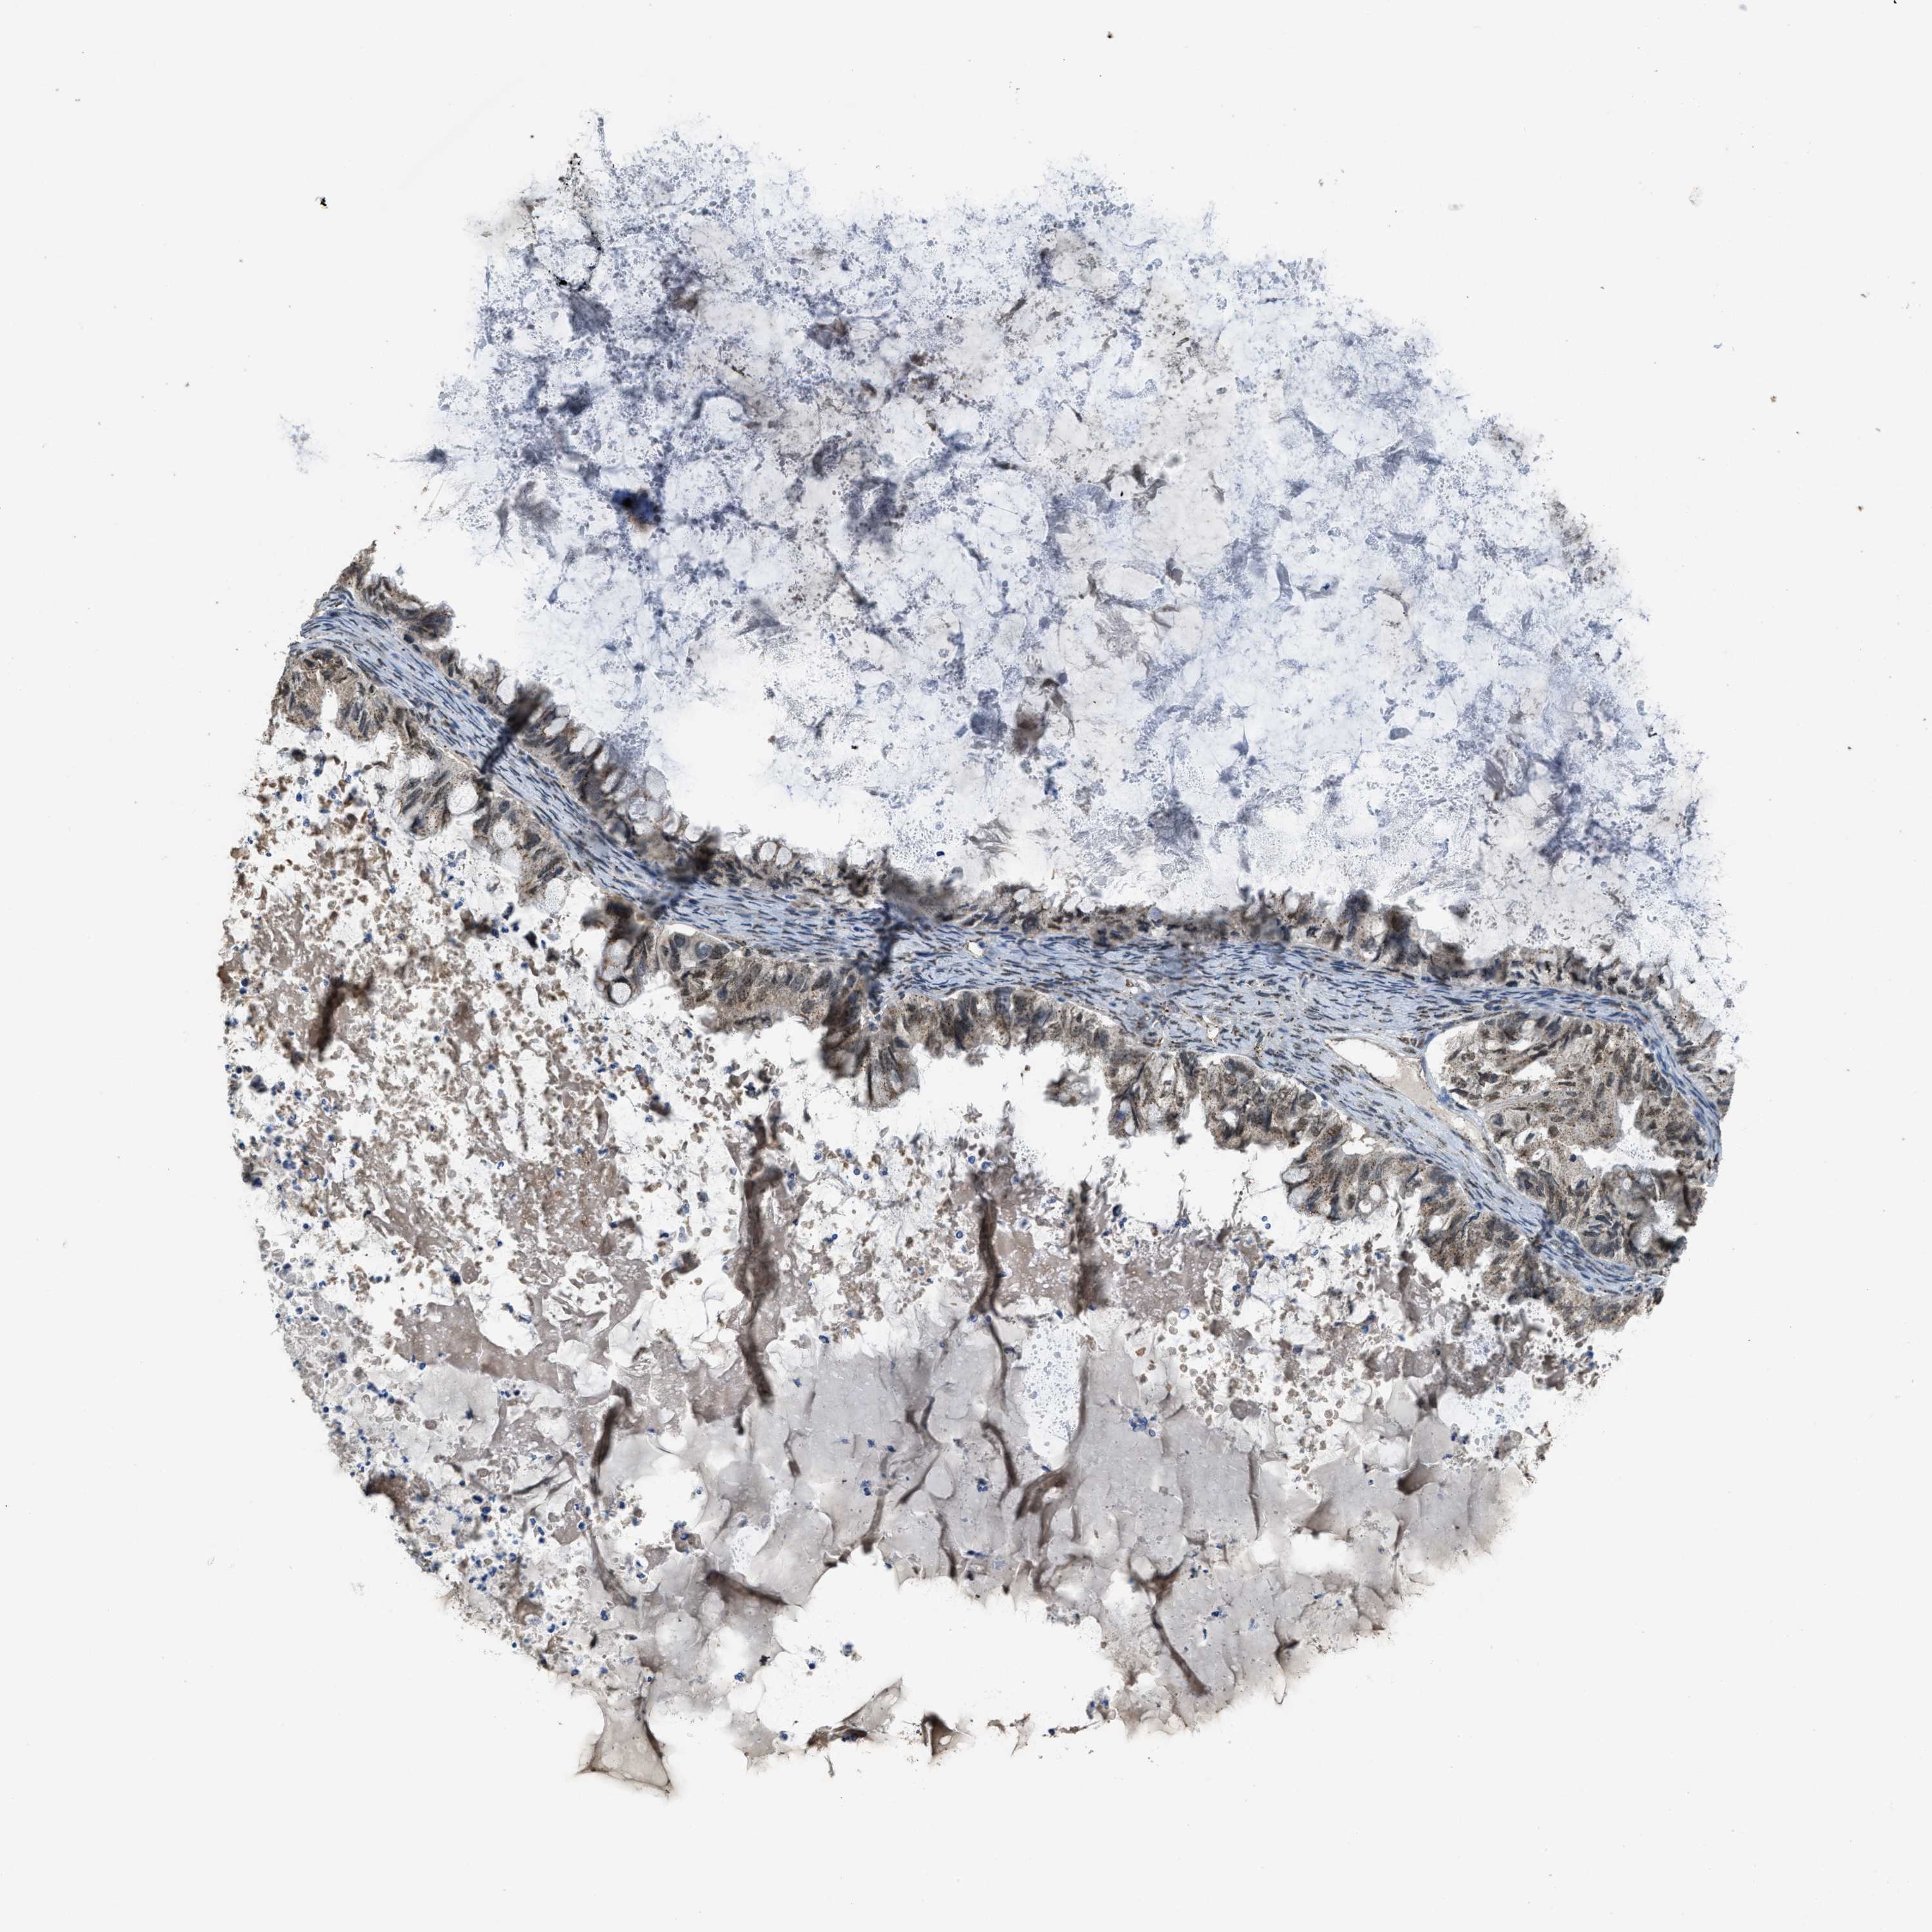

OVARIAN CANCER - Protein expressioni

A mouse-over function shows sample information and annotation data. Click on an image to view it in a full screen mode. Samples can be filtered based on level of antibody staining by selecting one or several of the following categories: high, medium, low and not detected. The assay and annotation is described here.

Note that samples used for immunohistochemistry by the Human Protein Atlas do not correspond to samples in the TCGA dataset.

Antibody stainingi

Antibody staining in the annotated cell types in the current human tissue is reported as not detected, low, medium, or high, based on conventional immunohistochemistry profiling in selected tissues. This score is based on the combination of the staining intensity and fraction of stained cells.

Each image is clickable and will lead to virtual microscopy that enables deeper exploration of all samples and also displays staining intensity scores, fraction scores and subcellular localization as well as patient and tissue information for each sample.

Antibody HPA019002

Staining

High

Medium

Low

Not detected

Intensity

Strong

Moderate

Weak

Negative

Quantity

>75%

75%-25%

<25%

None

Location

Nuclear

Cytoplasmic/membranous

Cytoplasmic/membranous,nuclear

Cystadenocarcinoma, serous, NOS

Carcinoma, endometroid

Cystadenocarcinoma, mucinous, NOS

Carcinoma, NOS